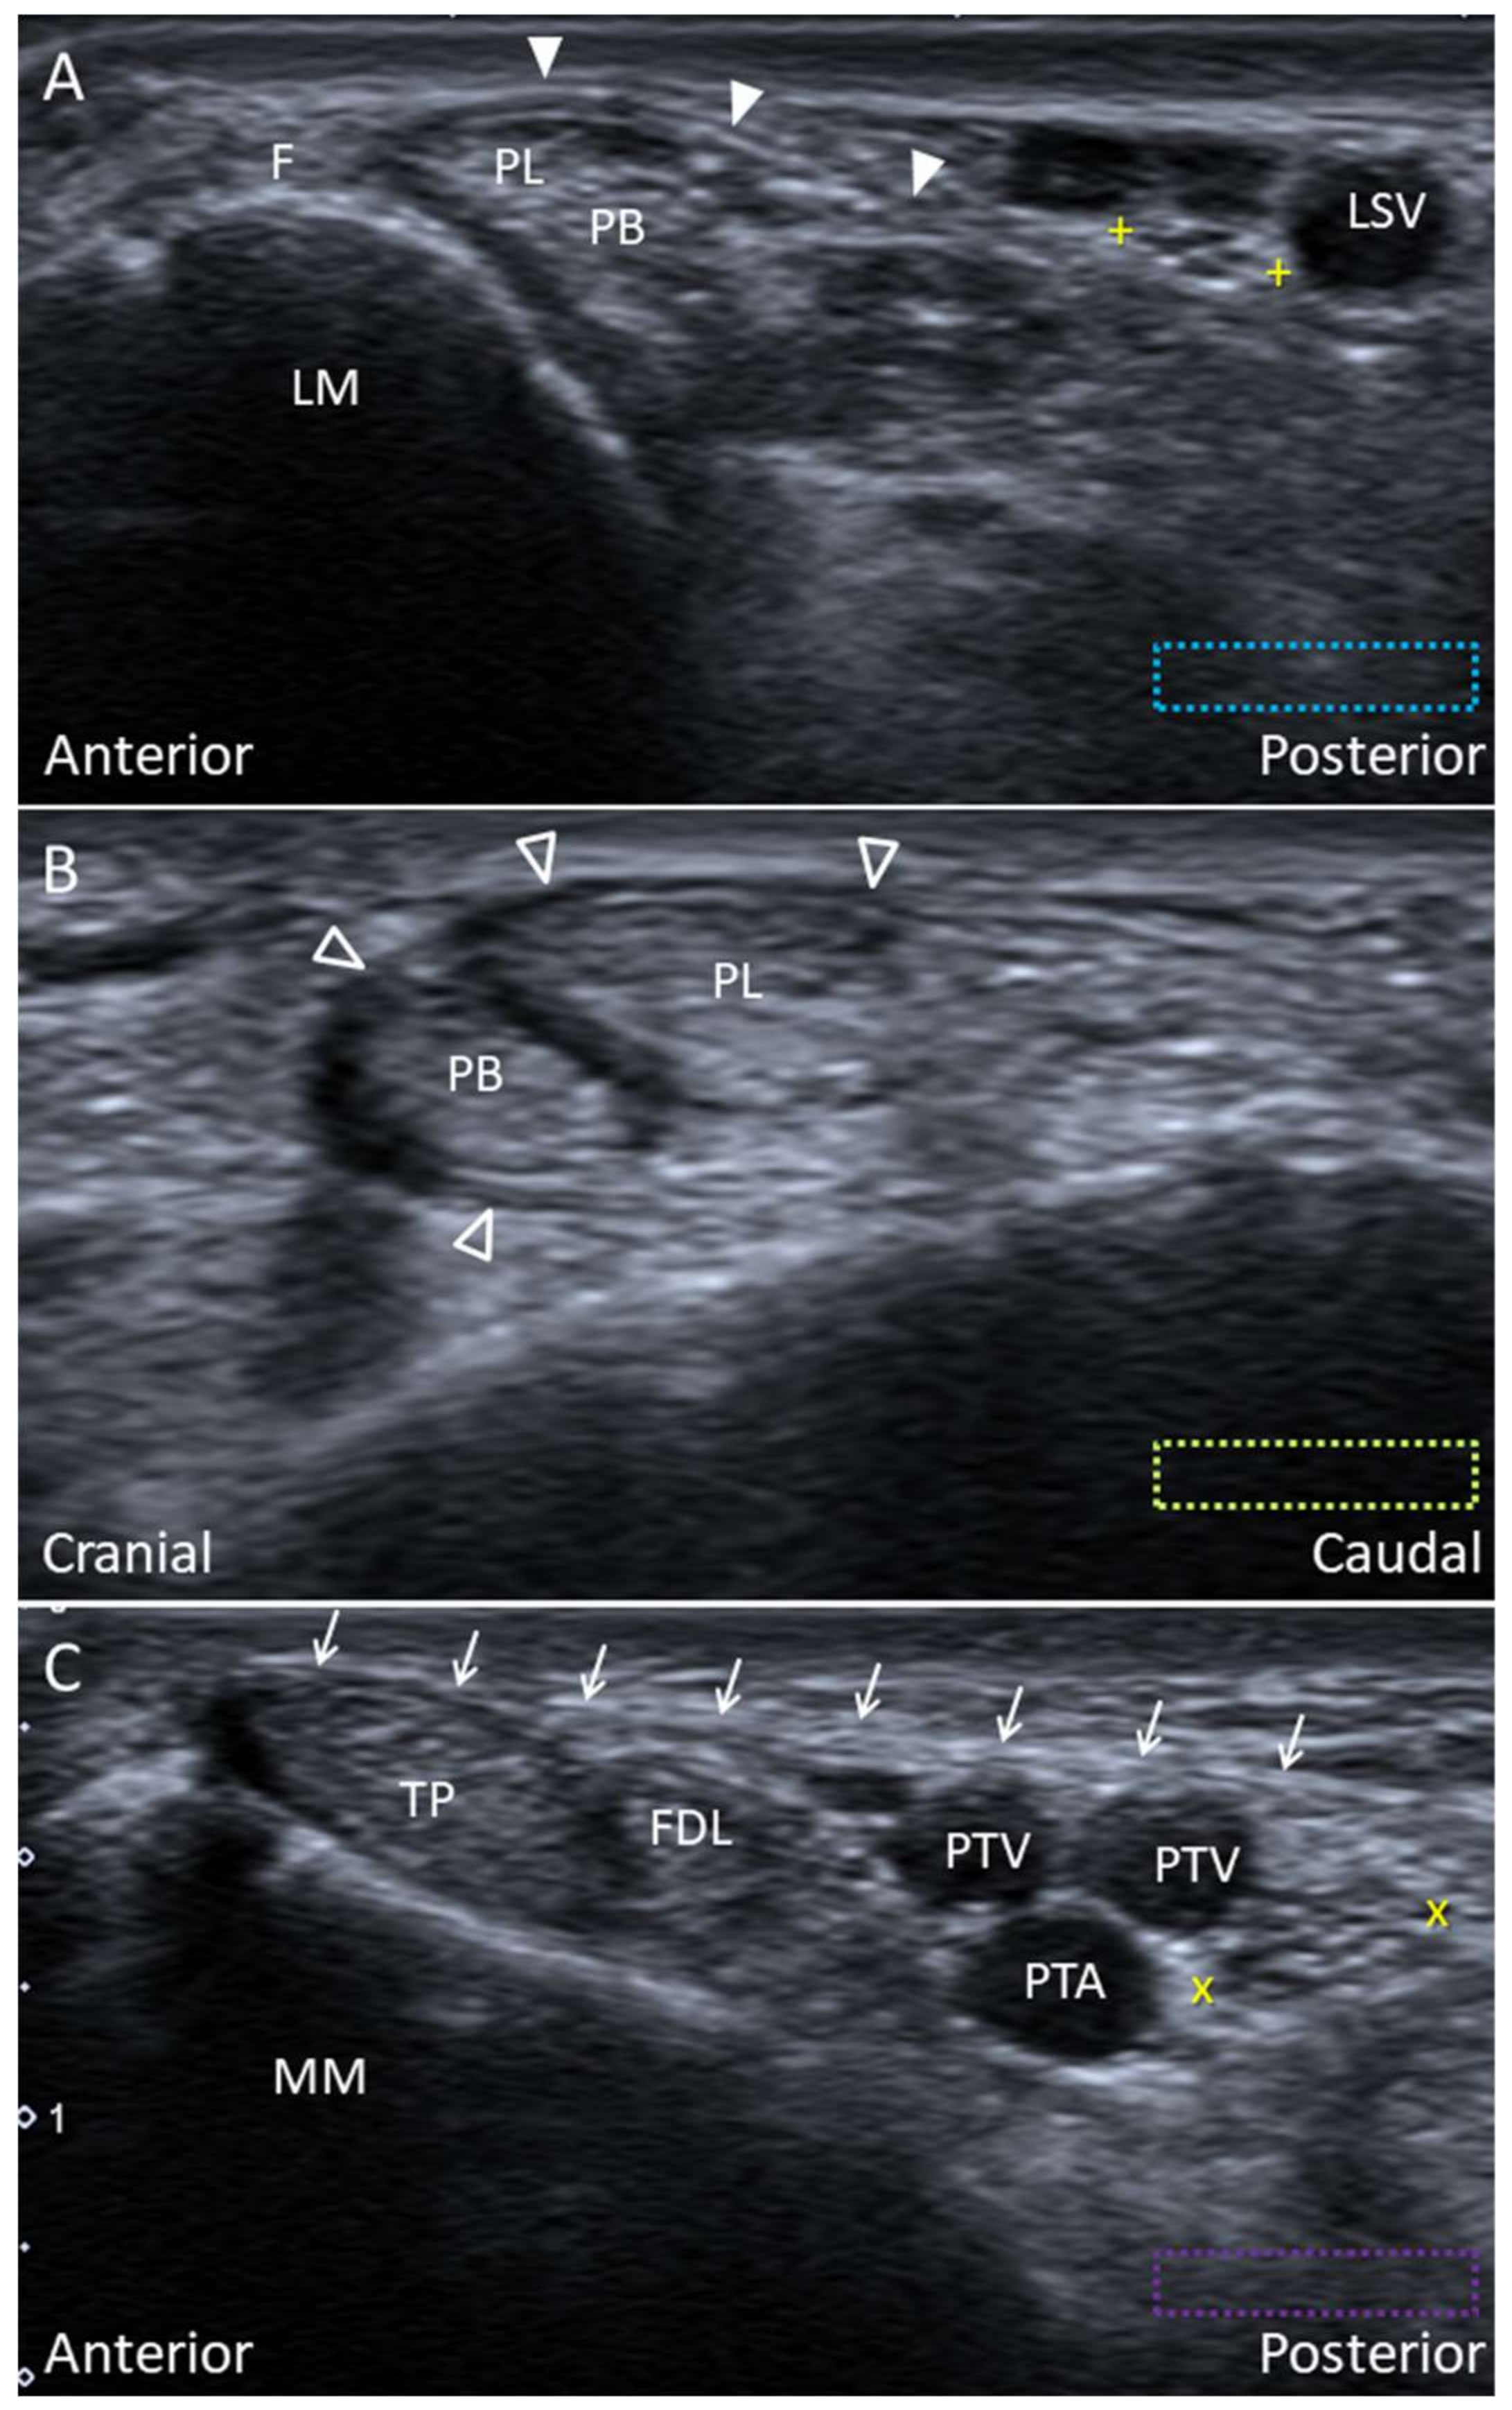

4.1. Peroneus Longus Tendon

4.1.1. Anatomy

4.1.2. Scanning Technique

4.1.3. Clinical Relevance

4.3. Tibialis Posterior Tendon

4.3.1. Anatomy

4.3.2. Scanning Technique

4.3.3. Clinical Relevance

4.4. Plantaris Tendon

4.4.1. Anatomy

4.4.2. Scanning Technique

4.4.3. Clinical Relevance